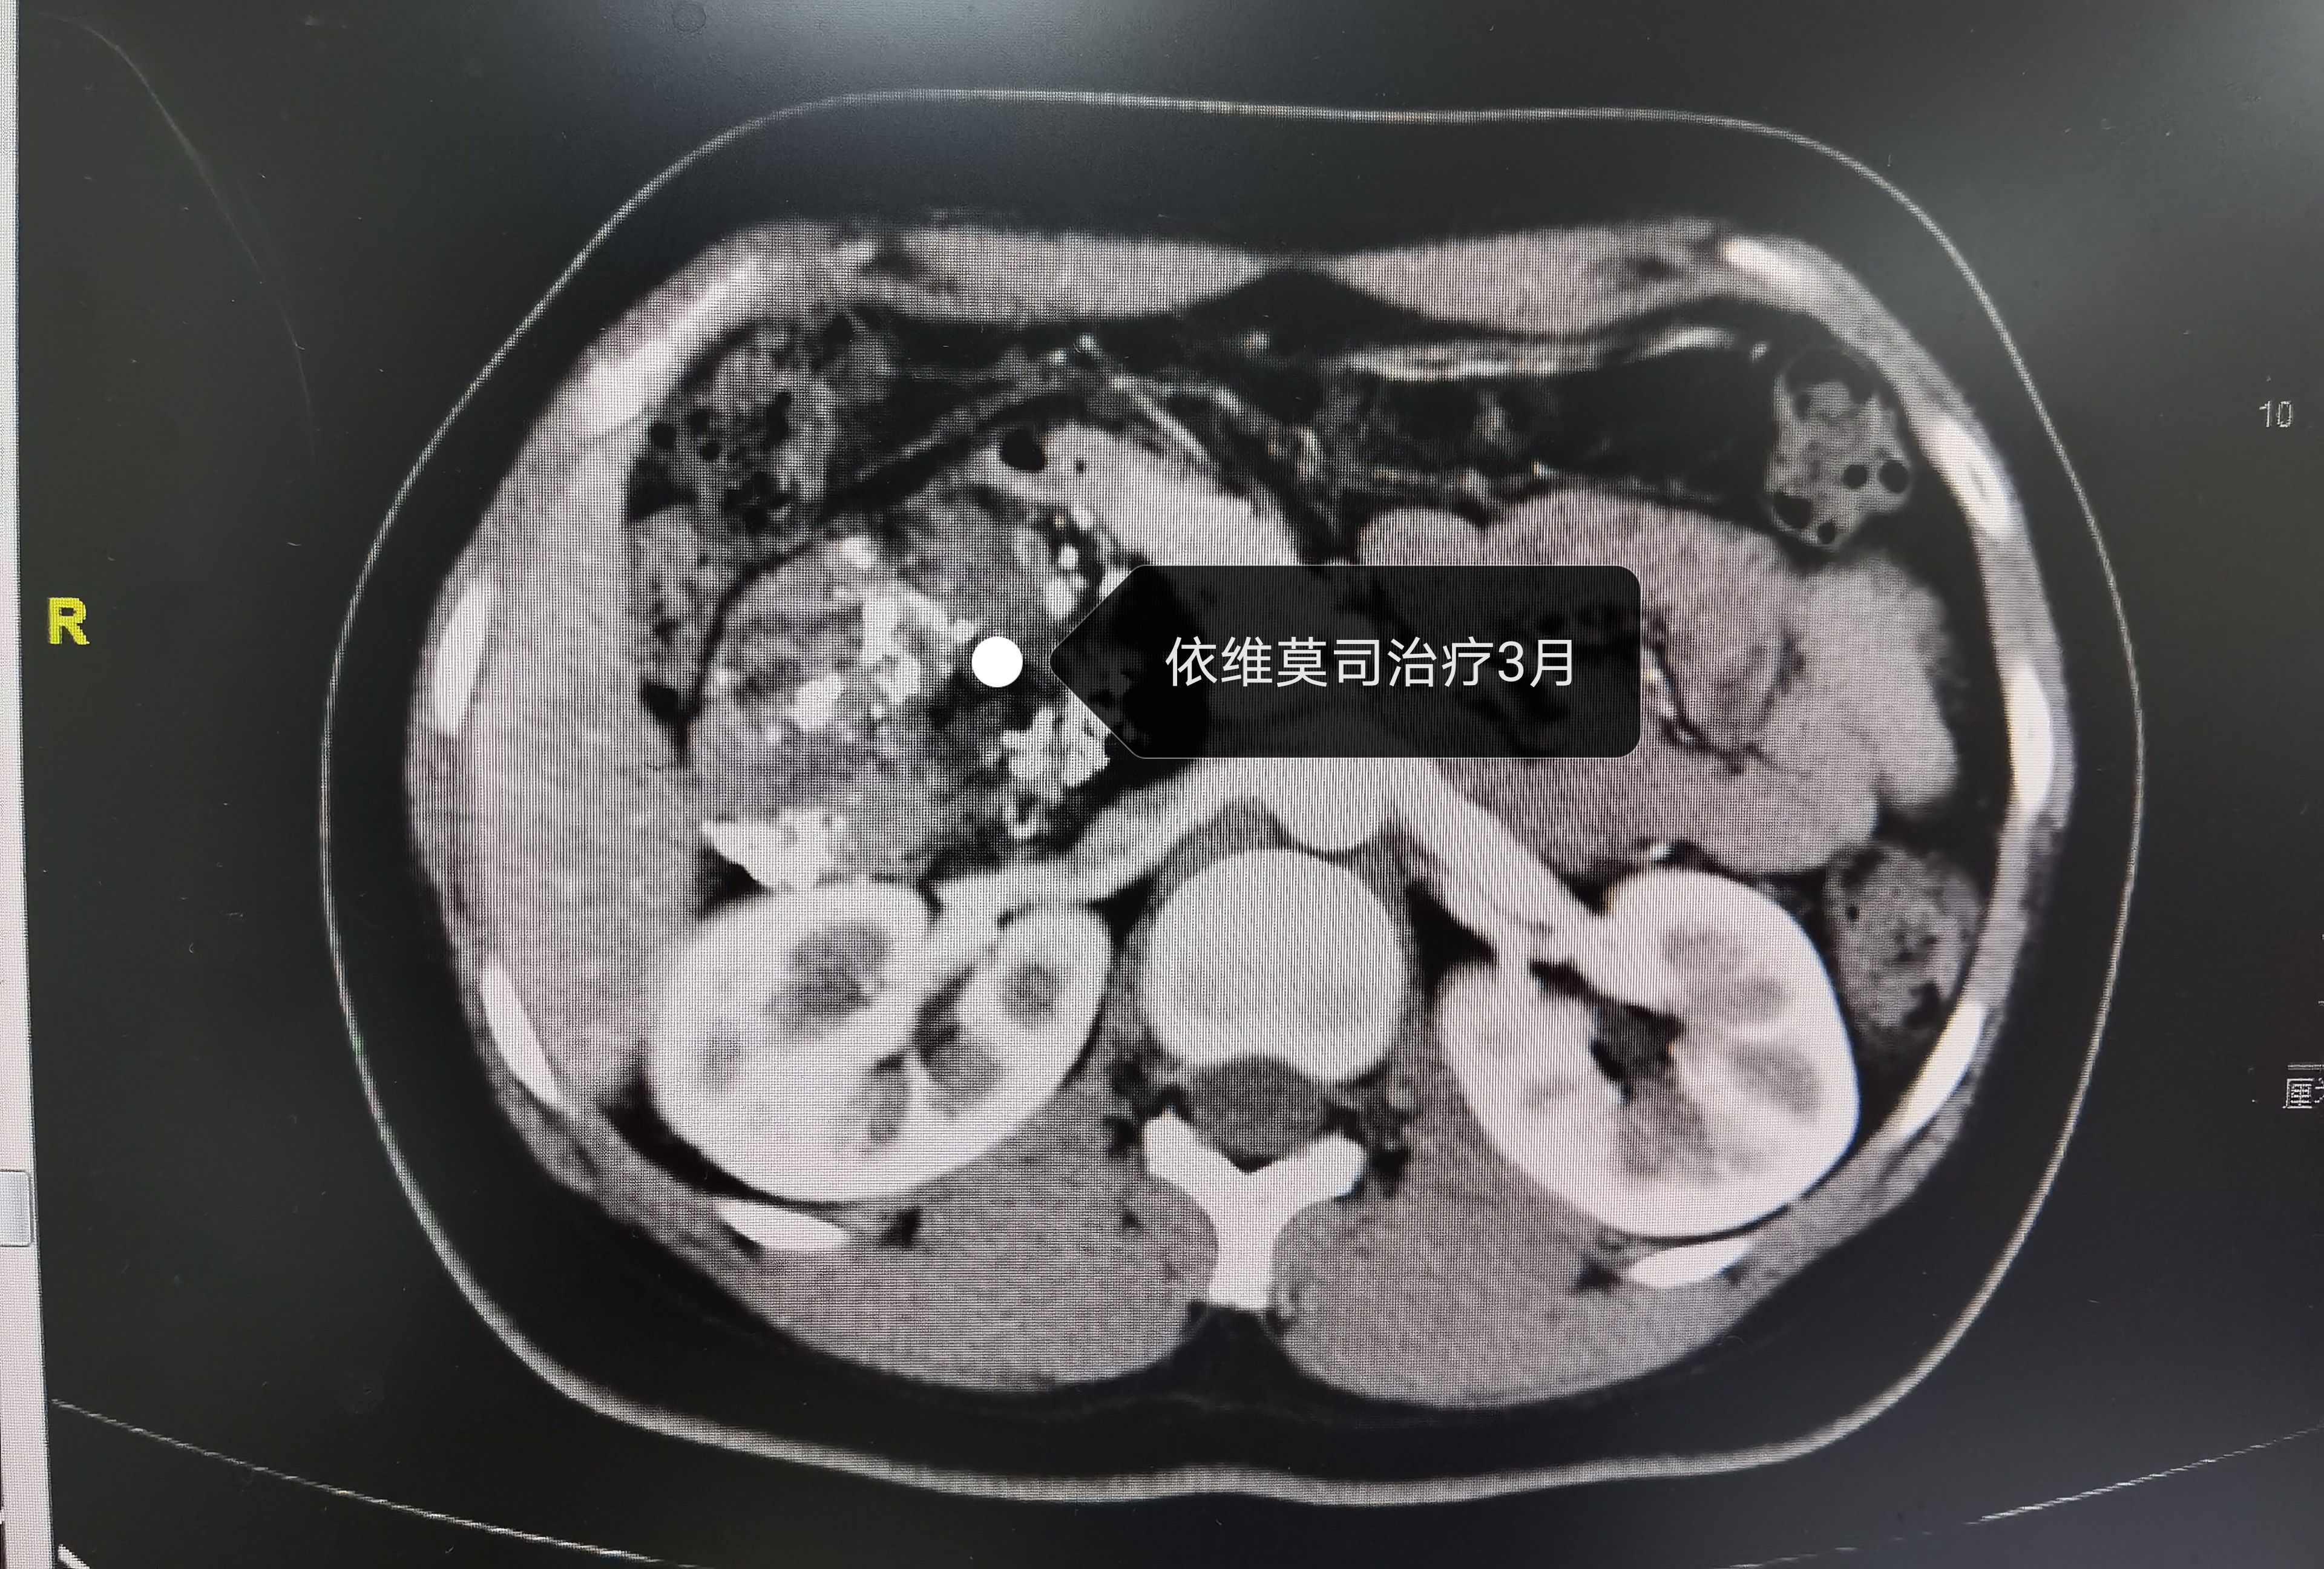

依维莫司治疗三个月

针对该情况,从2月份开始,经过我院MDT团队三次会诊,讨论了多种方案后,患者也同意了我们的方案,对我们寄予了厚望。过程很漫长,患者的依从性也是非常好,得到的结果更是喜人,会诊后我们对患者进行了介入科两次动脉栓塞,依维莫司治疗三个月,肿瘤较之前显著缩小。终于在今日(2020年 12月3日)进行了手术。